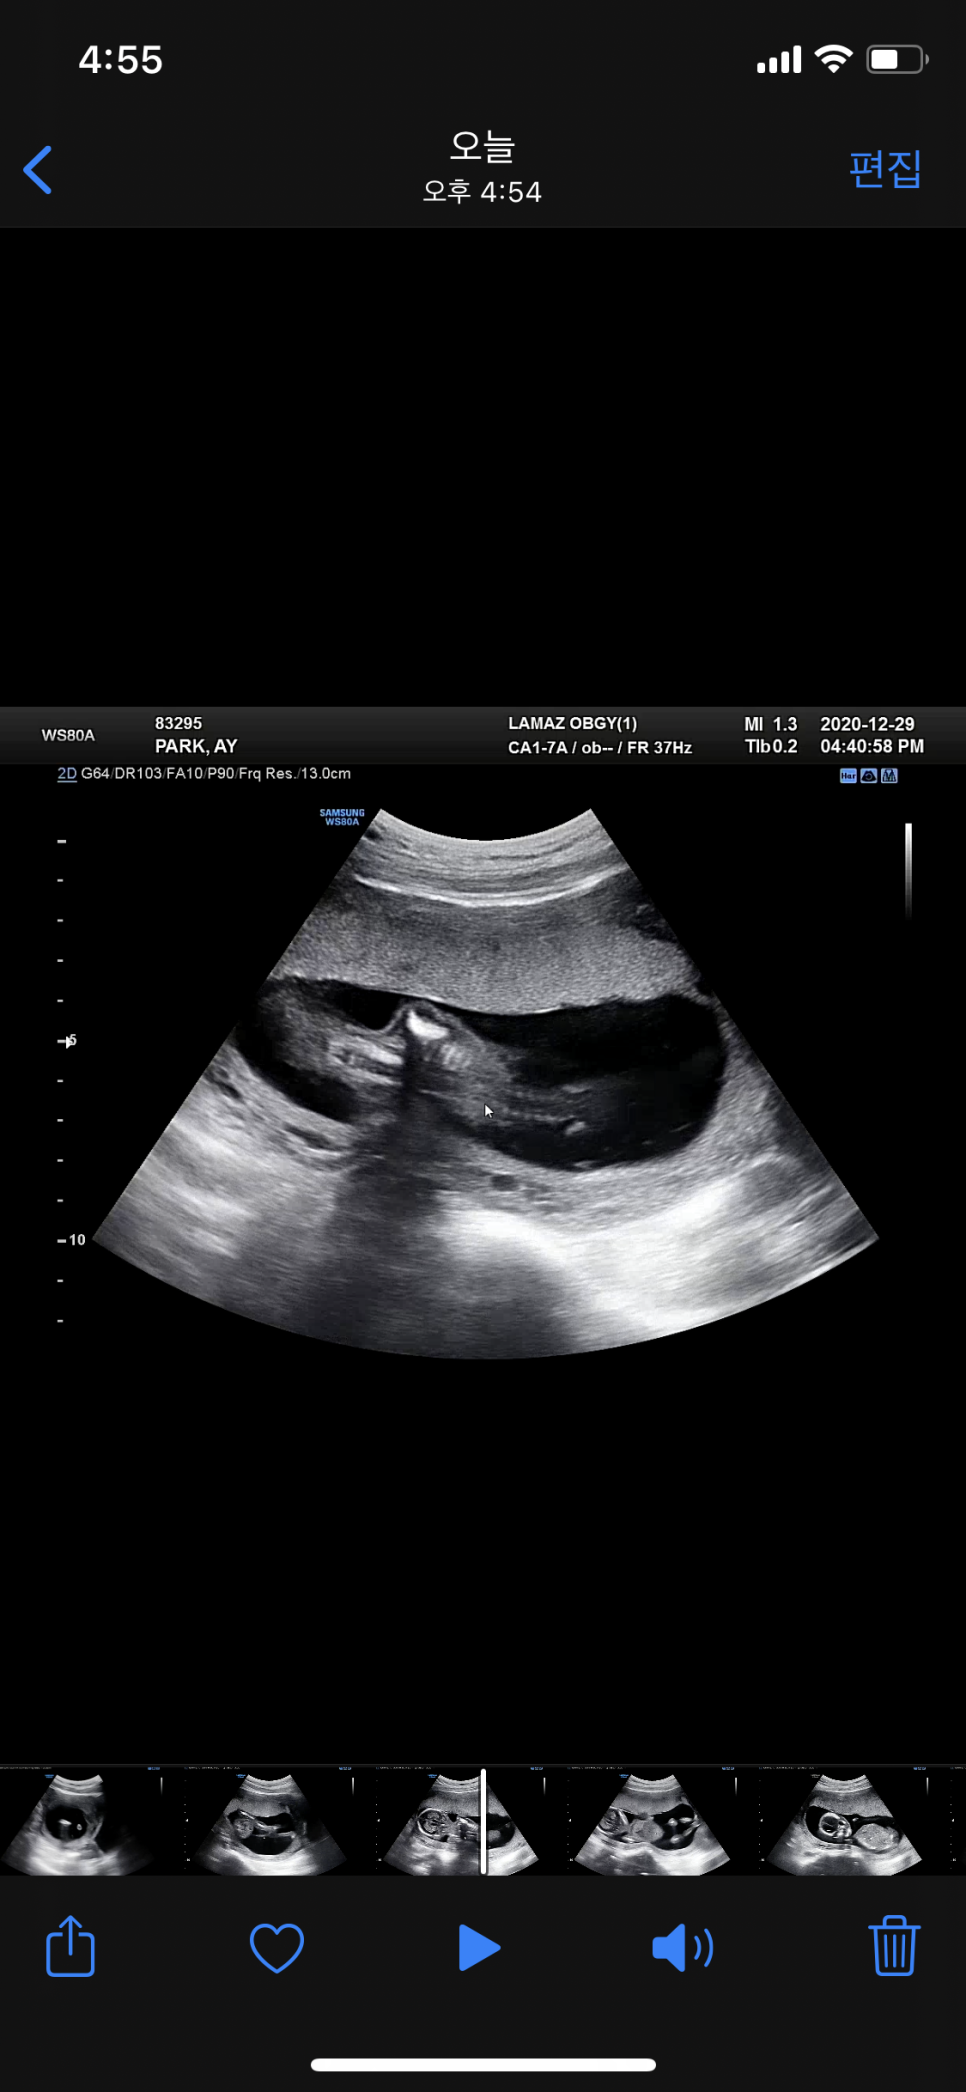

임신 16주 초음파

궁금했던 별똥별의 많은 분들이 아들 같다고 하셨지만 나름대로 성별 반전이 있었습니다.딸이었습니다! +_+